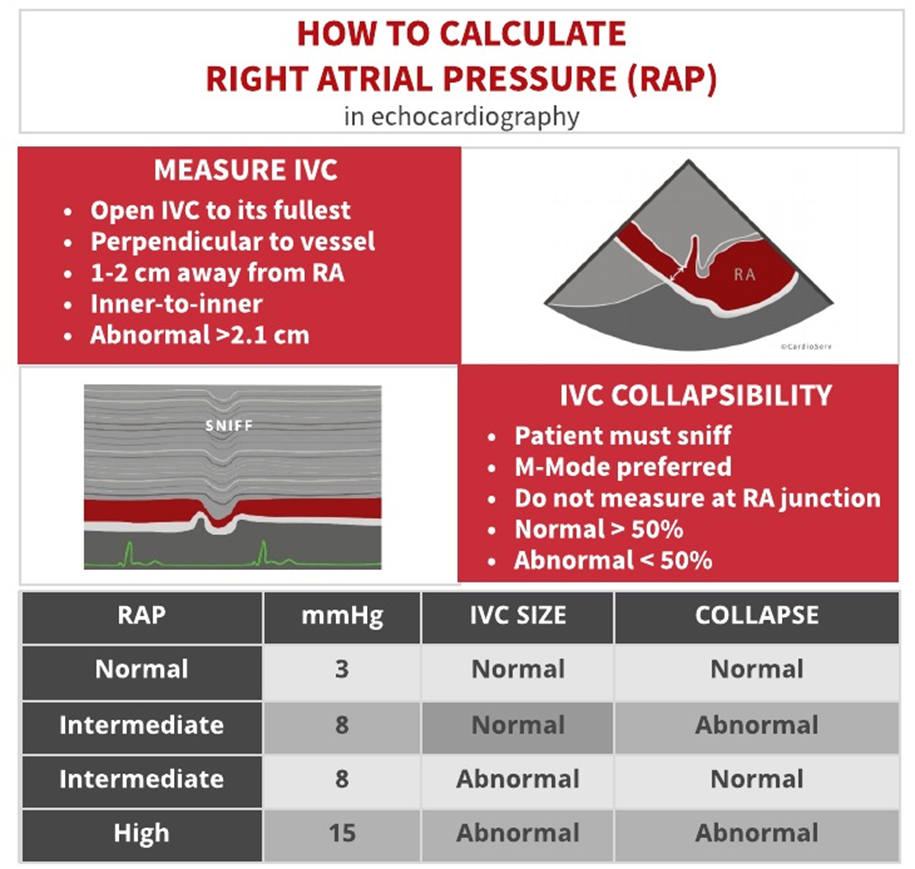

Right Ventricular Systolic Pressure (RVSP) is used to

RVSP is used to estimate right side pressures in the vessels leading to the lungs. This is used to determine pulmonary hypertension.

TR Vmax + RAP= RVSP

How to obtain the rsvp/spap

1. Place the CW cursor through the TR color jet

2. Measure the tricuspid regurgitant waveform to achieve the tr velocity

3. The machine will use the TR Vmax velocity and turn it into a pressure gradient. This is done by using the Bernoulli equation

If TR= 42MMHg+________

IVC=2.2

Add Sniff

=57

Ex? Since anything over 2.1 is abnormal and there was a sniff we add The high of 15. So 42+15= 57. If there was no sniff or the Ivc was 2.1 we would have added an 8 instead.

RVSP / Systolic pulmonary artery pressure (SPAP) determined by the TR

TR Max PG + RAP = RVSP/SPAP